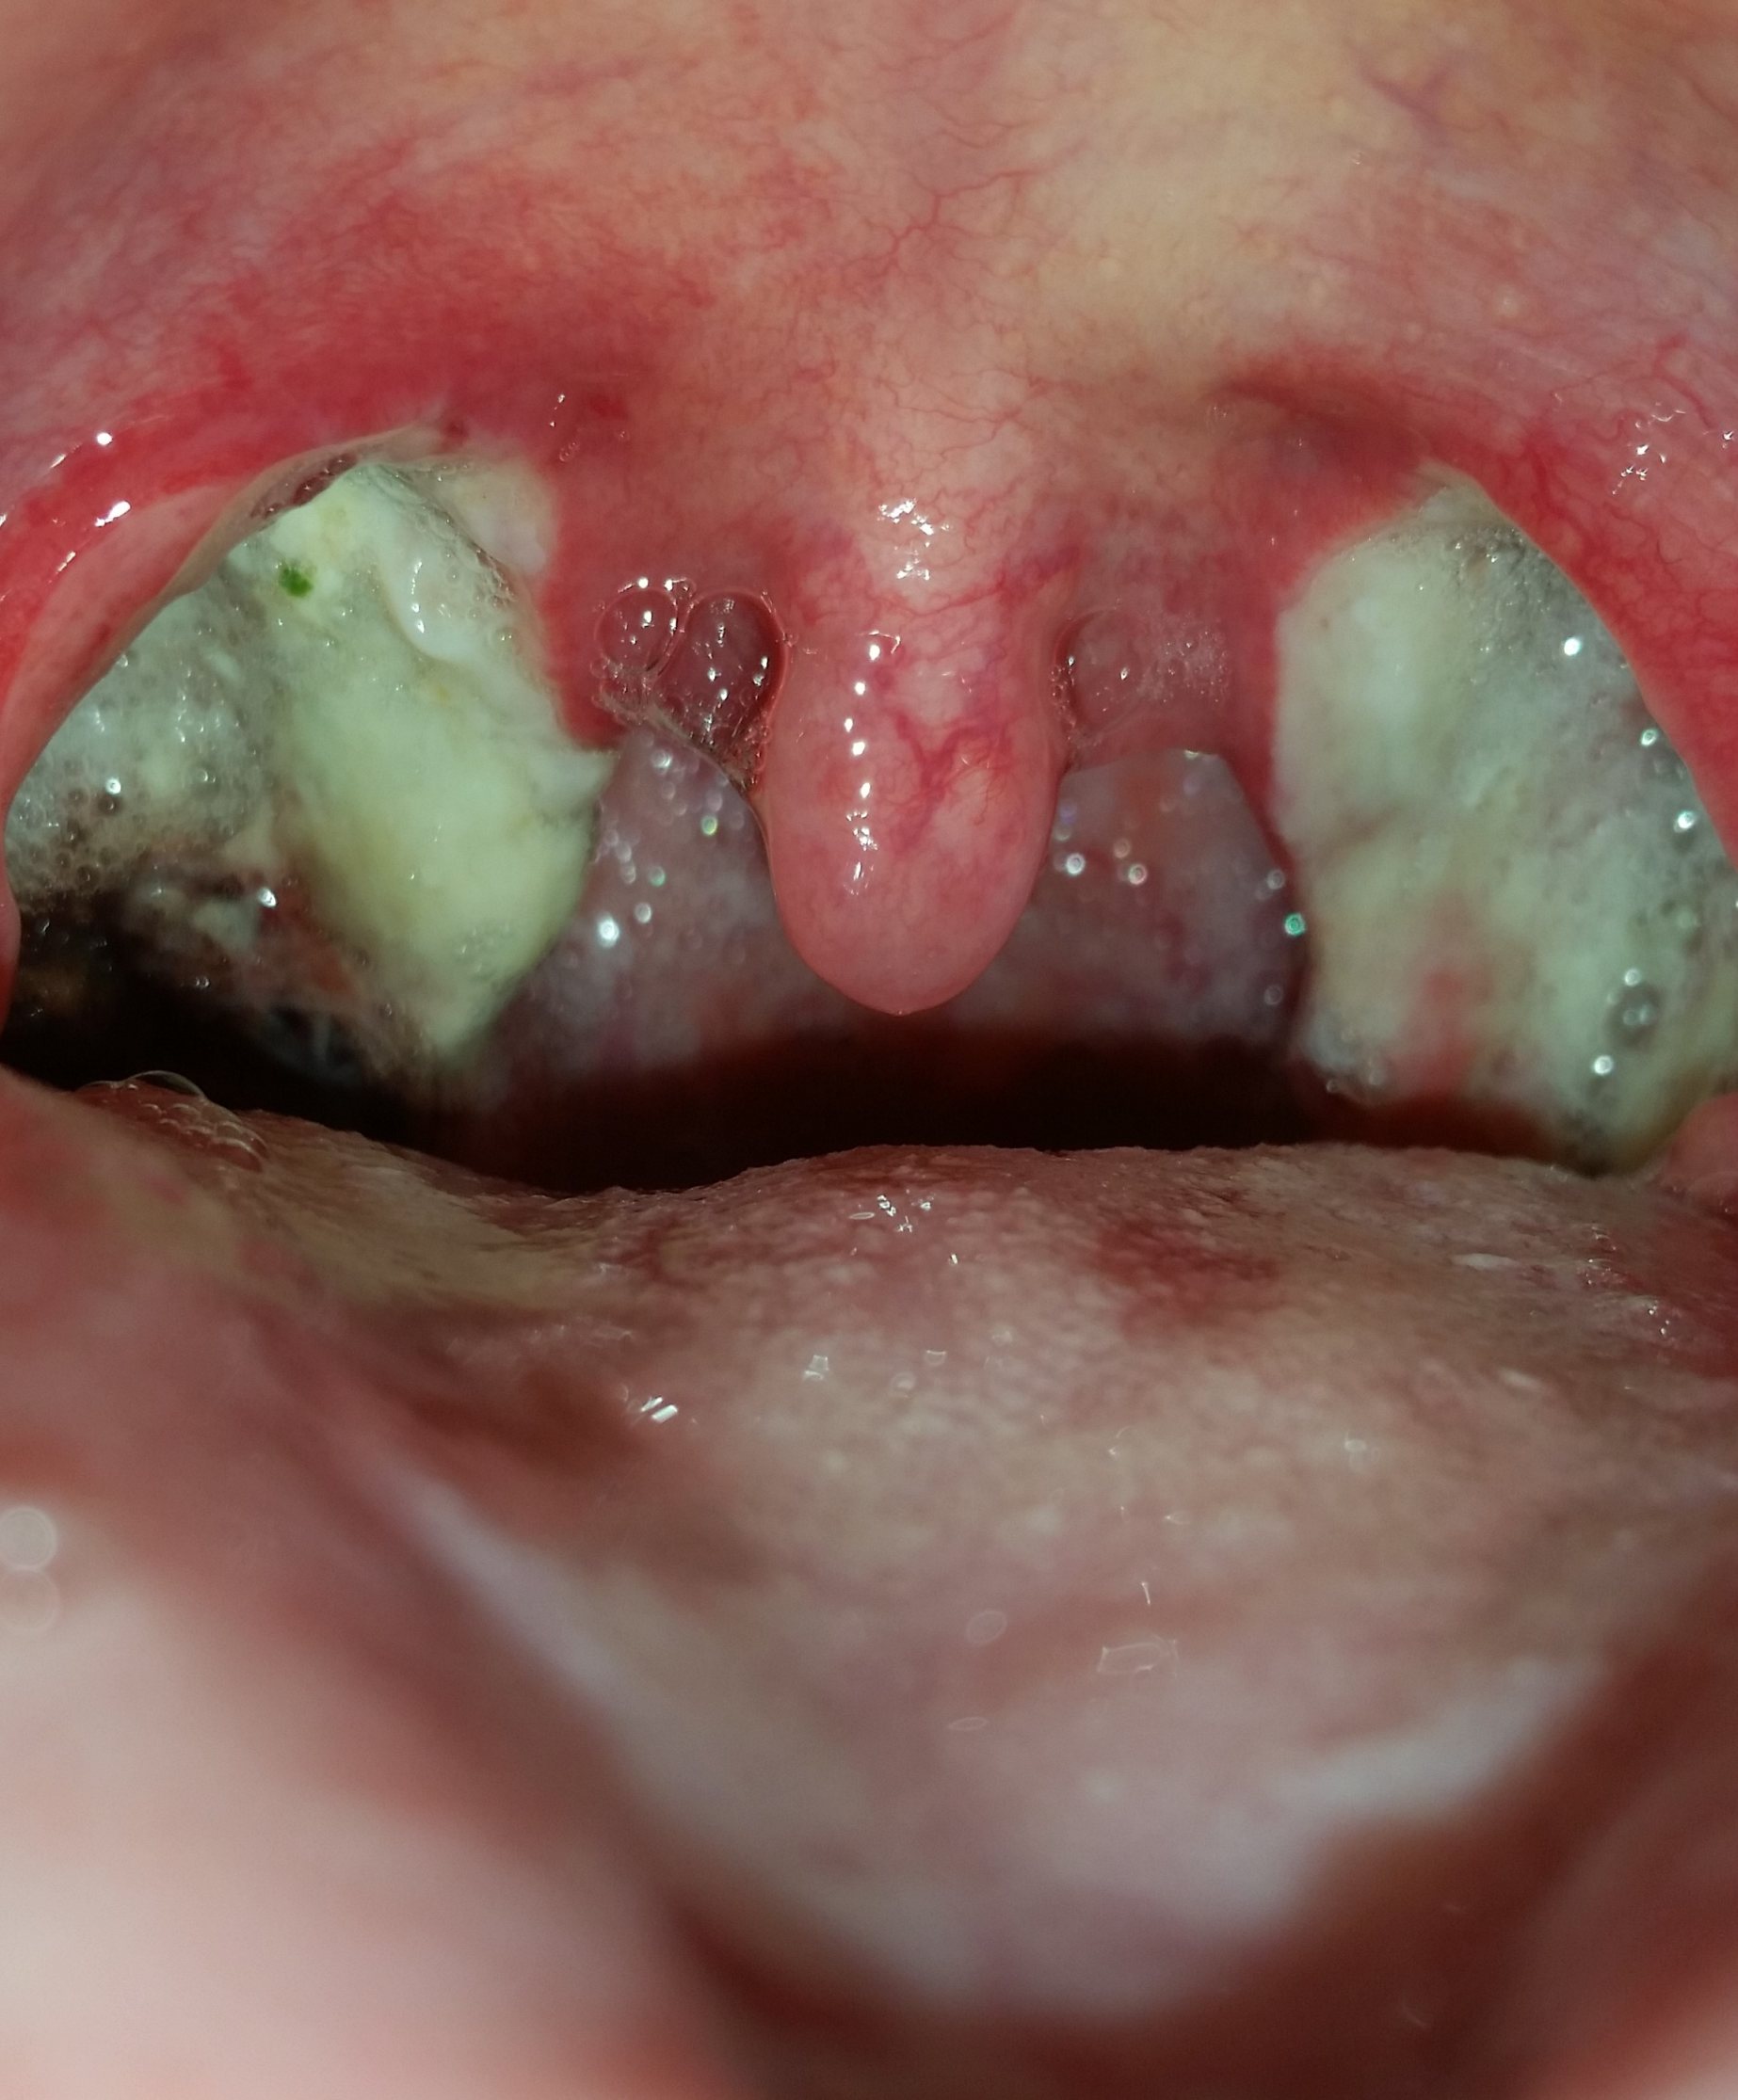

Mandel OP – Bilder Dokumentation Heilungsprozess

- Mandeloperation Tag 0

Nach der Operation bildeten sich direkt die weiß, grünlichen Beläge (Fibrinbeläge).

In der ersten Nacht erhielt ich aufgrund meines stark geschwollenen Halszäpfchen eine Cortison Infusion. Schmerzen hatte ich größenteils in der Nacht und am Morgen.